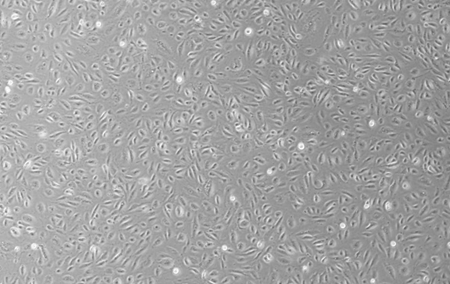

HUVEC(SCIENCELL) 人脐静脉内皮细胞是取自人脐静脉组织的原代内皮细胞通过SV40转化而获得的永生化细胞,合适条件下至少可以稳定传代20代以上。

5) 细胞生长方式:上皮样细胞,贴壁培养。

HUVEC(SCIENCELL) 人脐静脉内皮细胞在体外和体内模型中广泛用于研究血管生成。通过迁移、增殖和管状结构形成,模拟血管生成过程,在Matrigel上培养的HUVEC细胞可形成管状结构,用于评估血管生成能力。